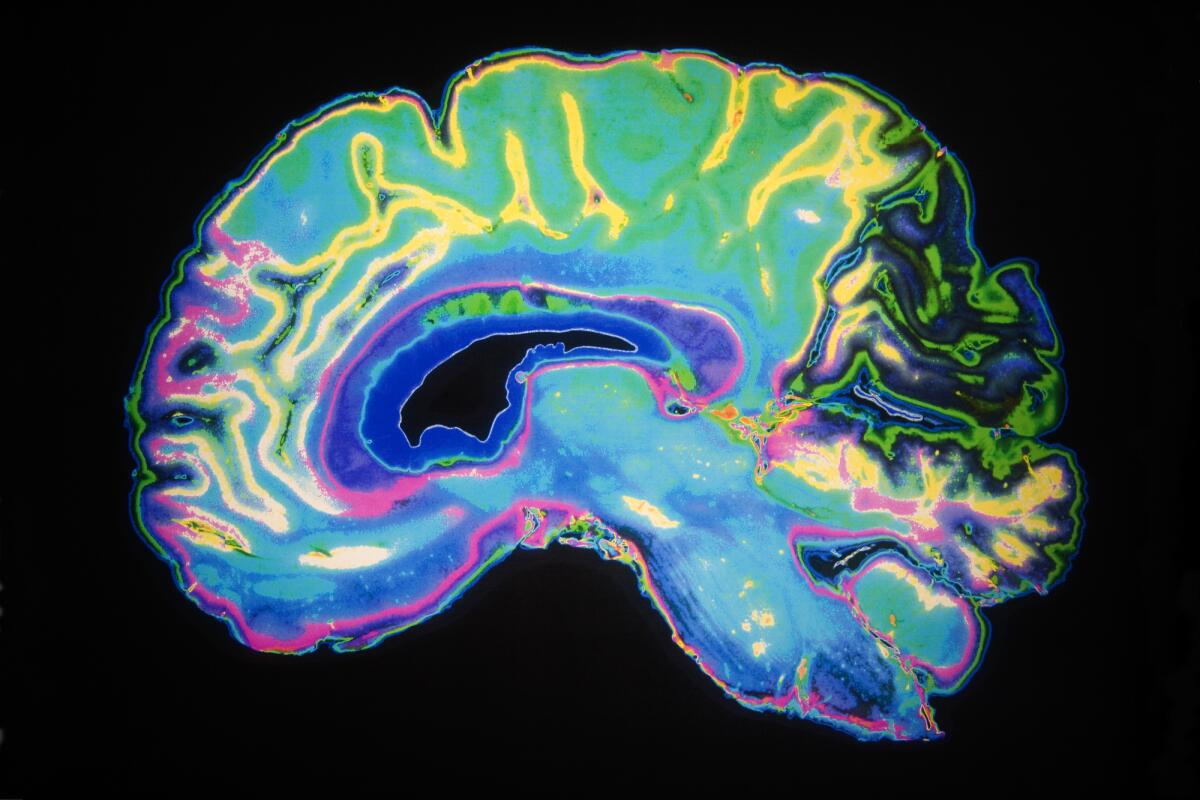

- МРТ головного мозга.